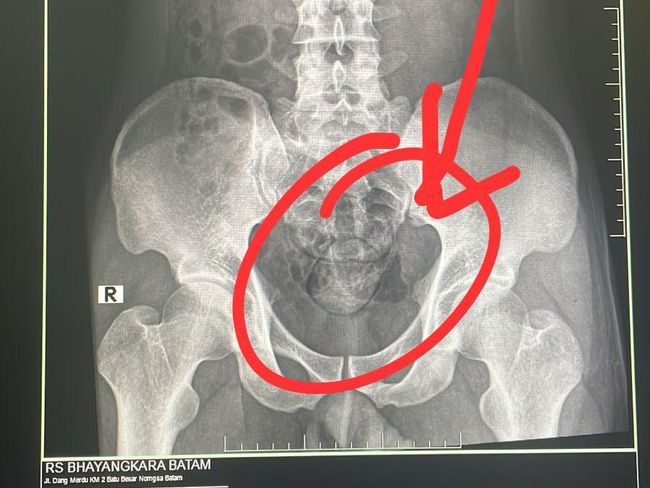

Foto: Penampakan hasil dari rontgen ditemukan dua buah kapsul berisi narkoba di dalam anus. (Foto: Polda Kepri)

Pelaku kemudian dibawa anggota Subdit 2 Ditresnarkoba Polda Kepri ke RS Bhayangkara untuk dilakukan rontgen di bagian radiologi.

"Hasil dari rontgen ditemukan dua buah kapsul di dalam perut. Selanjutnya pelaku mengeluarkan dua kapsul tersebut di toilet RS Bhayangkara. Total berat narkoba jenis sabu sebanyak 100 gram," ujarnya.